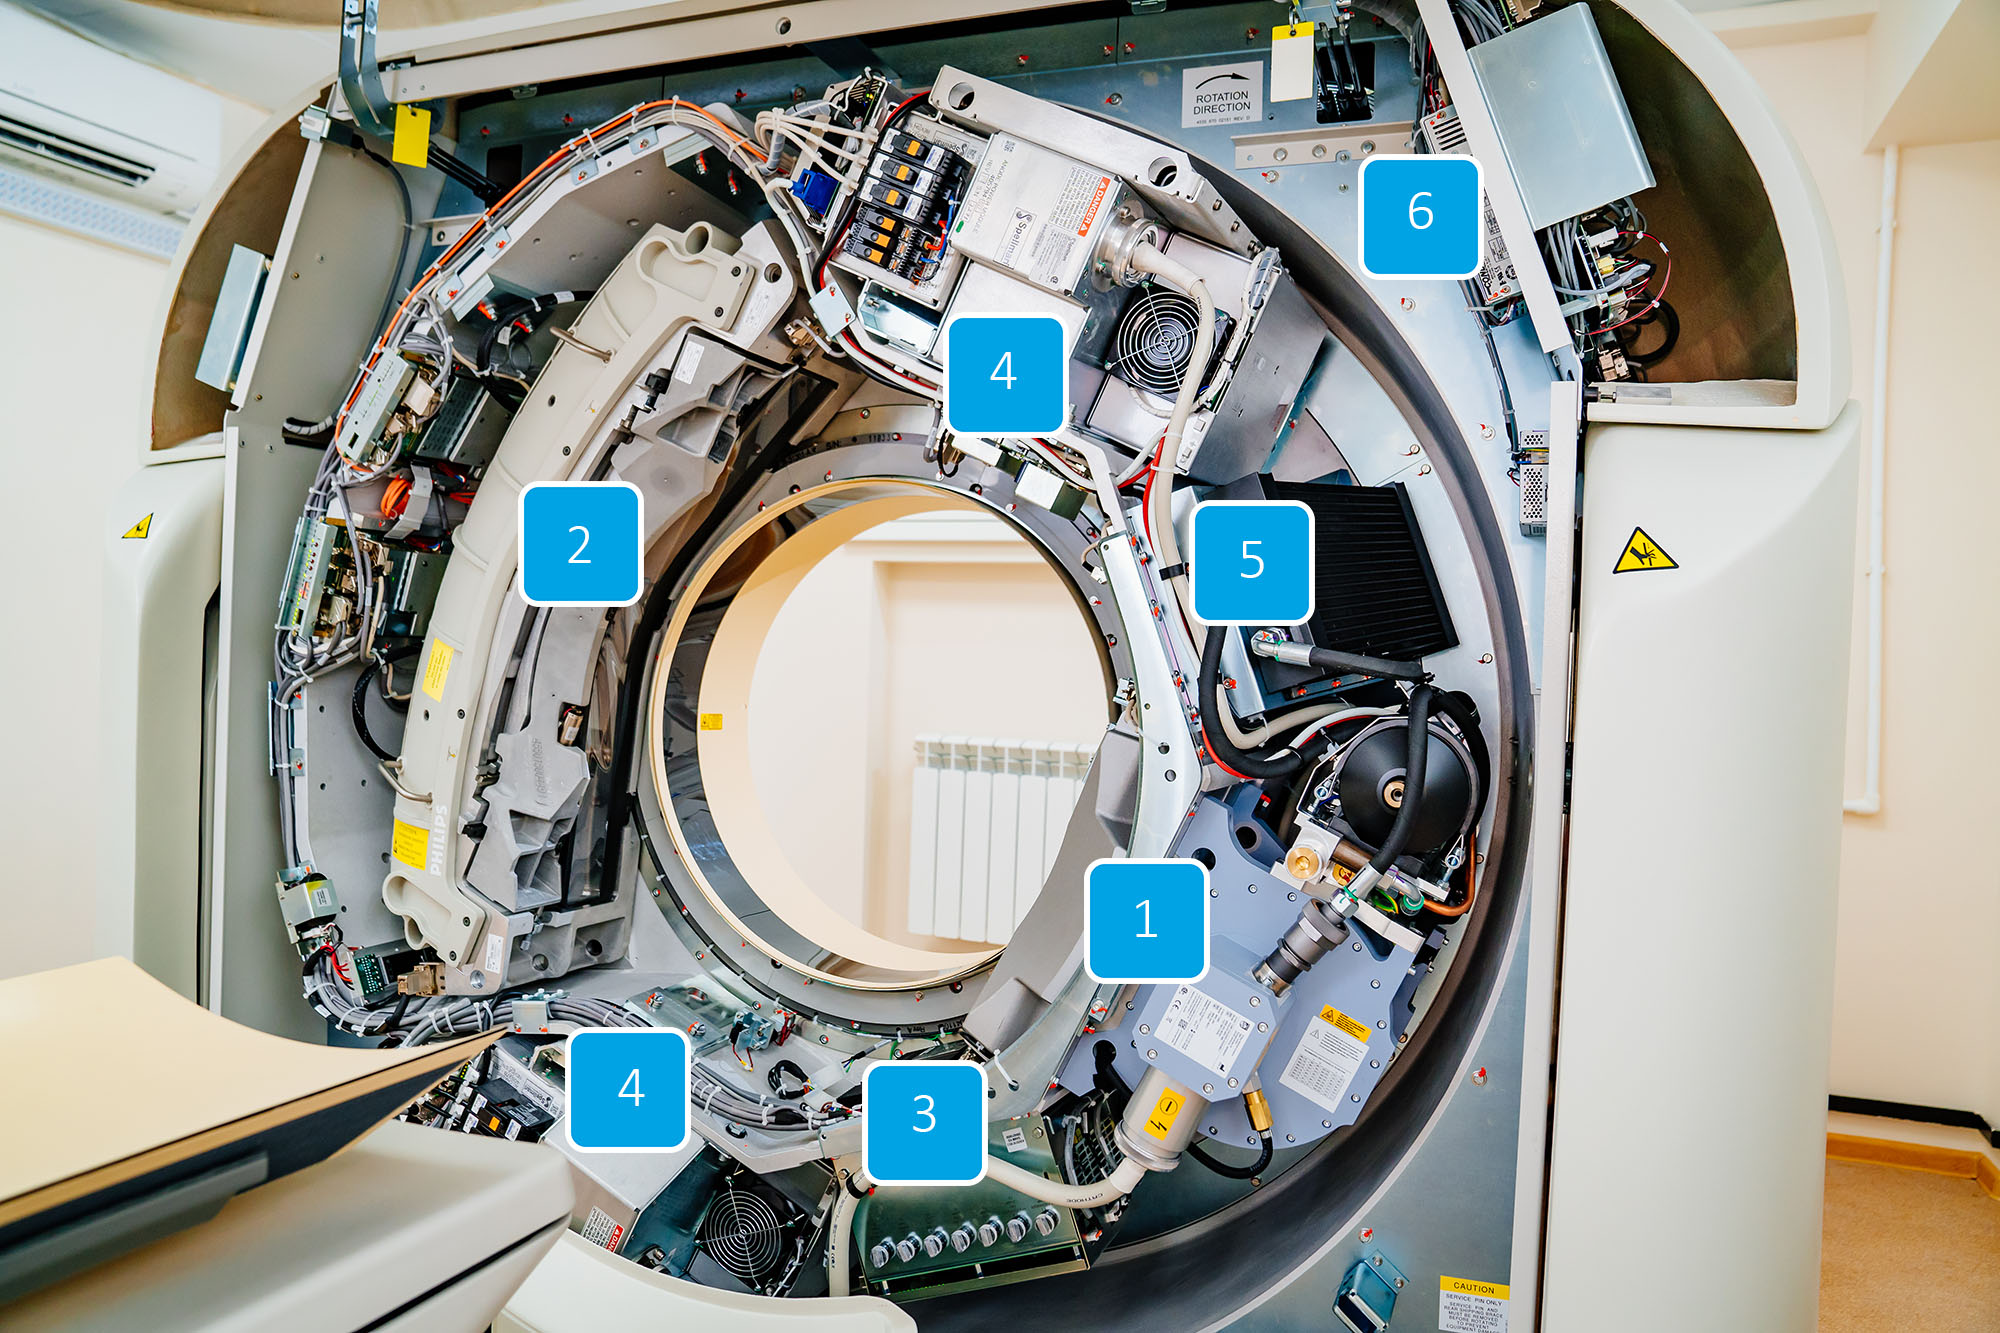

1. Гентри

Наиболее сложная и технически насыщенная часть аппарата, в которой происходит сканирование. Внутри кольцевого корпуса по кругу вращаются элементы:

- Рентгеновская трубка с коллиматором

- Система сбора данных

- Управление реле и предохранителей

- ВЧ генераторы

- Радиатор охлаждения рентгеновской трубки

- Блоки питания внутренних компонентов системы

Внутреннее устройство компьютерного томографа